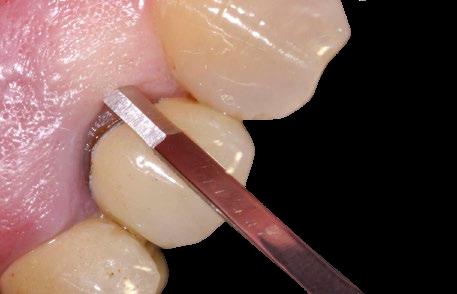

Imediátní implantace po extrakci

Okamžité zatížení implantátu

Management defektů tvrdých tkání